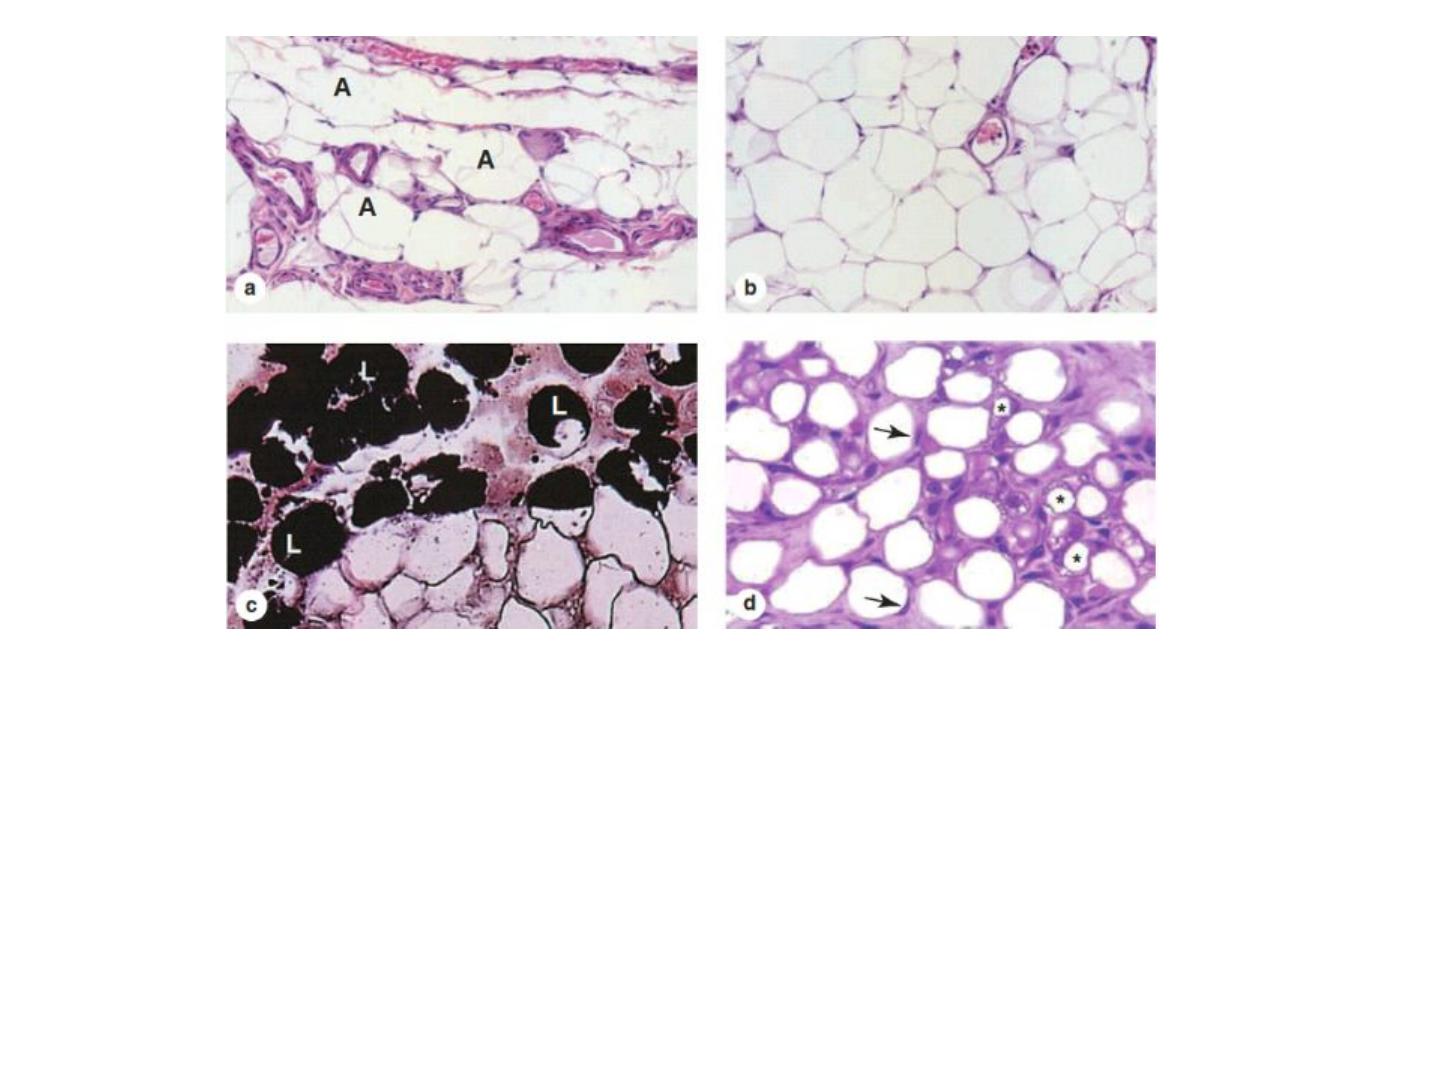

Figure 2: White or unilocular adipose tissue is commonly seen in sections of many human organs. (a)

Large white adipocytes (A) are seen in the connective tissue associated with small blood vessels. X100.

H&E. (b) Large (empty) adipocytes predominate in this typical white adipose tissue, which shows only a

small portion of microvasculature. X100. H&E. (c) Tissue was fixed here with osmium tetroxide, which

preserves lipid (L) and stains it black. Many adipocytes in this slide retain at least part of their large lipid

droplets. X440. (d) The specimen here was from a young mammal, and the adipocytes marked with

asterisks are not yet unilocular, having many small lipid droplets in their cytoplasm, which indicates that

their differentiation is not yet complete. The eccentric nuclei of unilocular cells are indicated by

arrowheads. X200.